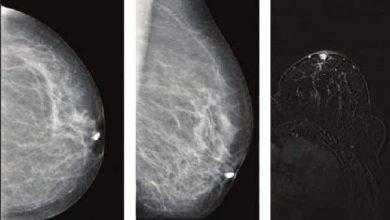

سیلان (أفرازات) الحلمة Nipple Discharge: يعدُّ الحملُ أو الإرضاع الطَّبیعي الرَّاھِن ھو التَّفسیر الأكثر وضوحاً لتَسرُّب سائل من الحَلَمة. كما…

الوَرَم الحُلَیمي القَنَوي Duct papilloma

الوَرَم الحُلَیمي القَنَوي Duct papilloma: وھو ورمٌ حميد داخل قَناة الثدي (الأنبوب الذي ينقل الحلیبَ من الغدَّة إلى الحلمَة)، يسبِّب…